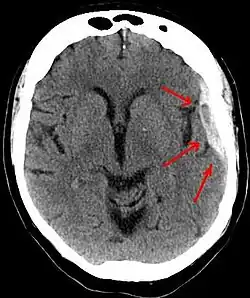

Subdurální hematom je druh traumatického poranění mozku, spočívající v krevní kolekci mezi tvrdou plenou mozkovou (dura mater) a pavučnicí (arachnoidea). Subdurální hematom mívá spíše poloměsíčitý tvar (na rozdíl od epidurálního hematomu, které má tvar spíše čočkovitý). Rozlišujeme tři typy subdurálního hematomu:

Hematom je vidět při CT vyšetření jako semilunární hyperdenzní útvar u kostí lebky (kalva).